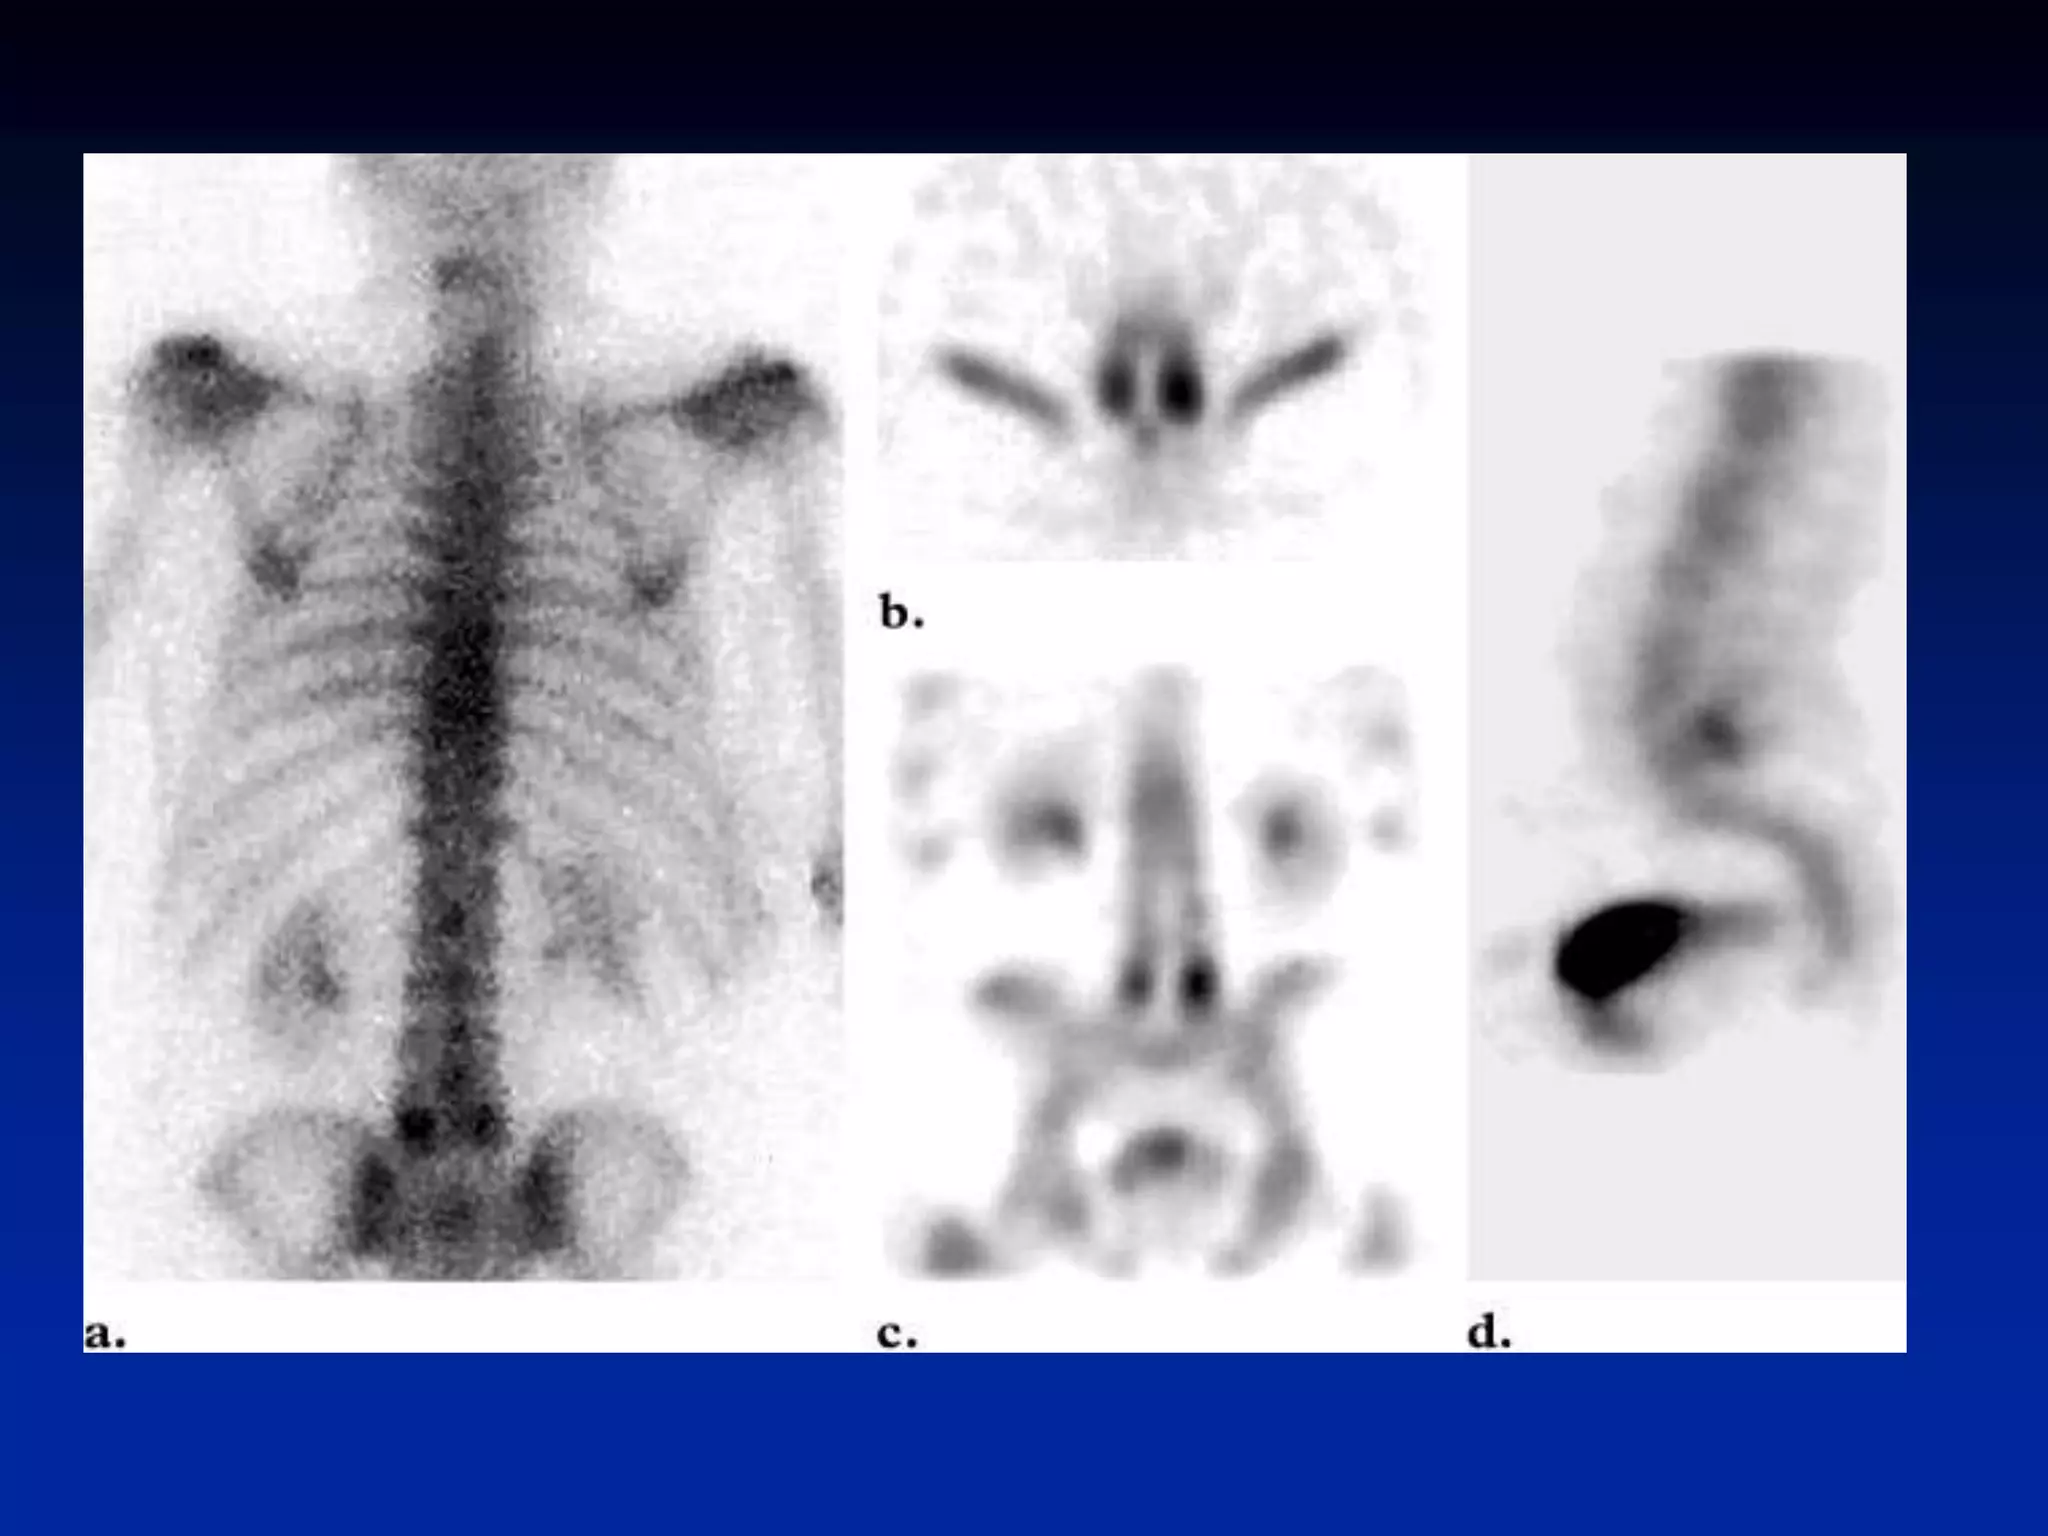

Superscan • When themetastatic process is diffuse, virtually all of the radiotracer is concentrated in the skeleton, with little or no activity in the soft tissues or urinary tract. The resulting pattern, which is characterized by excellent bone detail, is frequently referred to as a superscan • A superscan may also be associated with metabolic bone disease. Unlike in metastatic disease, however, the uptake in metabolic bone disease is more uniform in appearance and extends into the distal appendicular skeleton.

• 39.